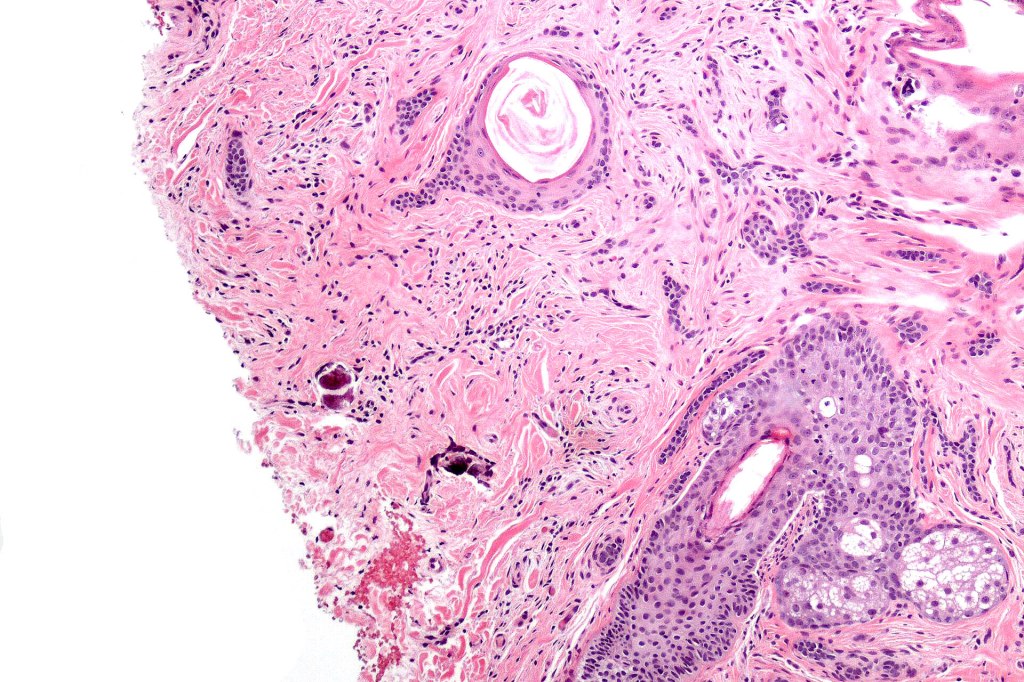

Histological features

•Consists of narrow epithelial strands & keratocysts embedded in a dense stroma

•Generally involves superficial & mid dermis but does not extend into the subcutaneous fat

•Calcification, foreign body giant cell reaction to keratin & bone are inconstant findings

•Epithelial stands may arise from follicular epithelium

•Co-existence with a dermal nevus is sometimes encountered